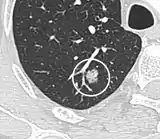

| Lung nodule | |

A lung nodule or pulmonary nodule is a relatively small focal density in the lung. A solitary pulmonary nodule (SPN) or coin lesion,[1] is a mass in the lung smaller than three centimeters in diameter. A pulmonary micronodule has a diameter of less than three millimetres.[2] There may also be multiple nodules.